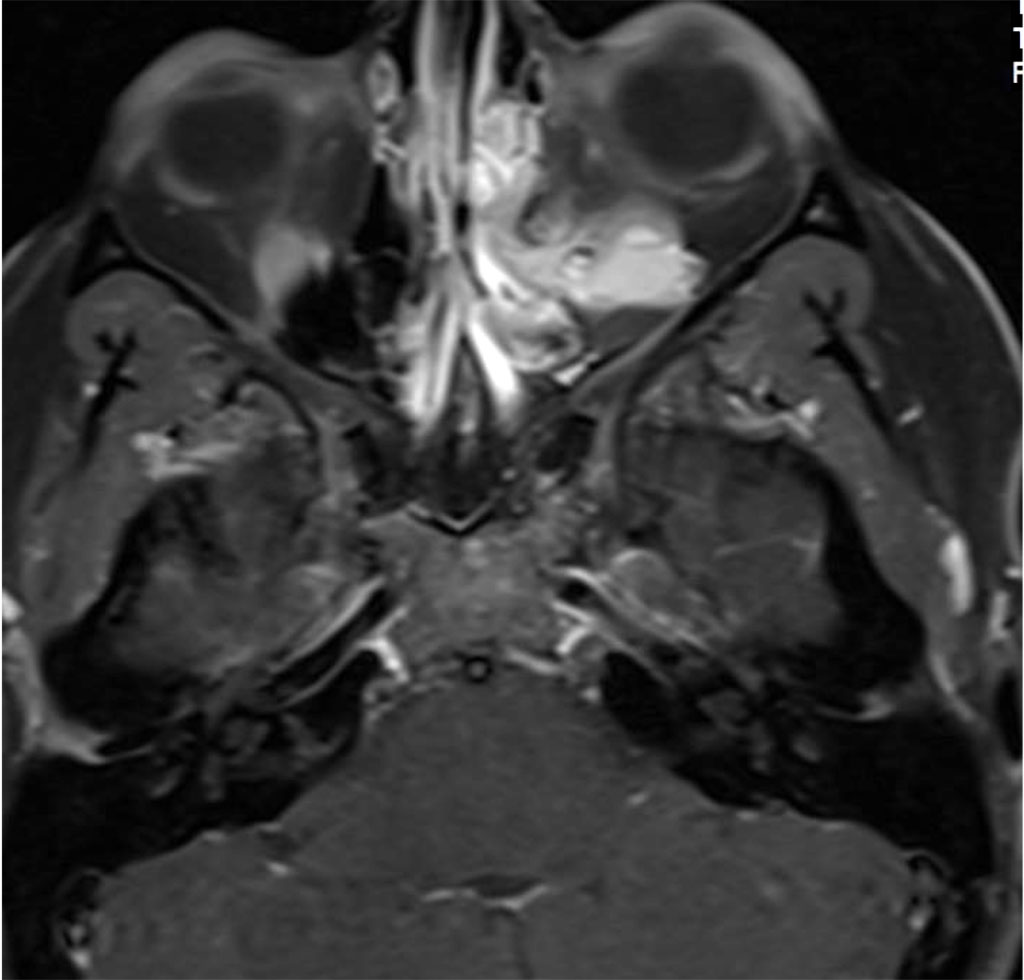

Her symptoms began and increased during her second pregnancy. She was not pregnant at the time of presentation. Magnetic resonance imaging (MRI) with Gadolinium and fat suppression revealed a large vascular lesion in the left orbit (Figures 2a,b).

Figure 2a: Axial MR T1 with contrast demonstrating intra and extraconal orbital lesion